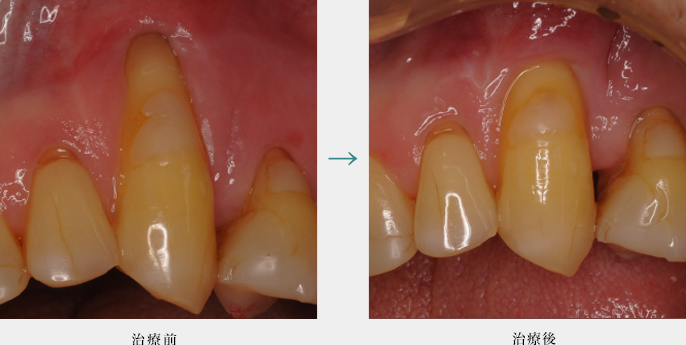

ダイレクトボンディング

ダイレクトボンディングによる健全な歯質を温存した虫歯治療(前歯)

健全な歯質は削らず物性に優れた樹脂を詰めています